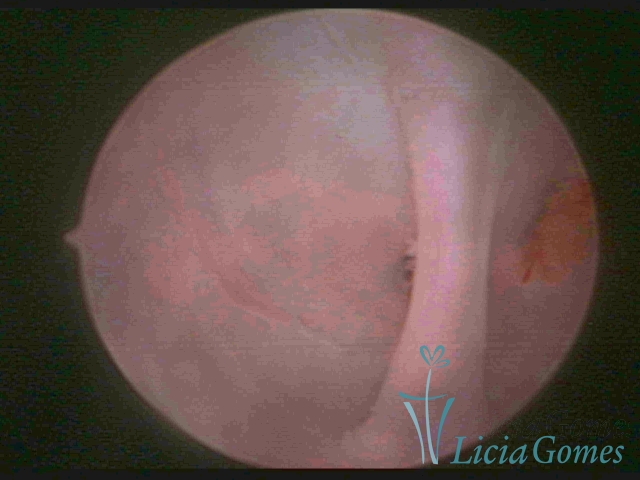

Septate uterus

It probably occurs by the lack of resorption on the middle line, in the merge of Müllerian ducts. The uterus is divided by a partial or total septum which is viewed as a crossbar, not covered by endometrium, which not bleeds when sectioned.

Complete septum when it occupies the whole extension of the cavity, dividing it into two hemicavities.

When this septum occupies only a part of the extension of the uterine cavity, it is considered as incomplete.